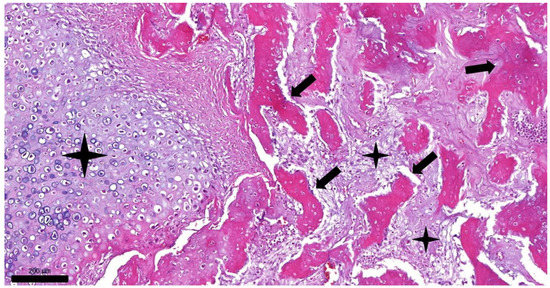

2. Case Presentation

2.2. Results